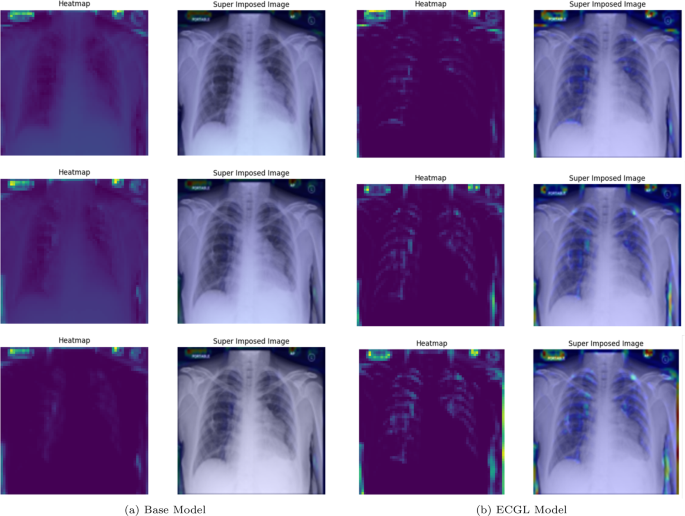

Likewise, Figs. 6 and 7 compare the proposed ECGL model and the Base model in terms of explainability by using GradCAM heatmaps. While both models generally seem to be focusing on similar areas (central region) of the chest X-rays, the color intensity in the heatmaps and superimposed images obtained from the ECGL model clearly shows a greater emphasis on certain regions that are related to the respiratory system and pneumonia disease. As it can be seen in Fig. 4(a) and 4(b) (correctly labeled instances), the highlighted regions of the Base model are more blurred, hazy, and spread out across the image, suggesting that the model’s decisions are less interpretable and apparent to the experts. Whereas the proposed ECGL model presents more focused and localized highlighted regions, showing that the model is primarily relying on specific areas of the image, relating to the particular region attacked by the disease, to make its prediction. The ECGL model makes it easier to understand the model’s reasoning and therefore presents more explainability. In addition, the ECGL model produces a more concentrated heatmap, indicating more confidence in prediction.

GradCAM Heatmaps (left column) and Superimposed images (right column) of the (a) Base model and (b) ECGL model for correctly labeled instances. The illustrated heatmaps correspond to GradCAM visualizations for labels 0 (normal), 1 (pneumonia present), and 2 (pneumonia absent, abnormalities exist), arranged from top to bottom, respectively

GradCAM Heatmaps (left column) and Superimposed images (right column) of the (a) Base model and (b) ECGL model for incorrectly labeled instances. The illustrated heatmaps correspond to GradCAM visualizations for labels 0 (normal), 1 (pneumonia present), and 2 (pneumonia absent, abnormalities exist), arranged from top to bottom, respectively

Moreover, in spite of both models’ similar performance illustrated in Fig. 5(a) and 5(b), the GradCAM visualizations clearly demonstrate noticeable differences. The Base model resulted in a more scattered visualization that may not correspond to the actual pathology. This indicates that the Base model’s prediction can be based on irrelevant features and not focused on the main required regions. The proposedECGL model, on the other hand, highlighted regions that are more relevant to the considered medical condition, suggesting that the constraints have helped the model focus on more meaningful features.

Unlike the Based model, the ECGL model’s heatmap for the incorrect prediction is more localized, highlighting a specific region in the lung. The overlay shows that there is indeed an abnormality in this area, but it could have been insufficient to confidently classify the image, which resulted in an incorrect final prediction. While such false predictions highlight the complexity of the task, the findings suggest that adding the constraints and guiding the model with domain-specific explanations through proposed ECGL can enhance the model’s explainability even when overall accuracy remains quite the same. Using such explainability, the experts can better identify the model’s deficiencies and limitations, leading to efficient mitigation of them.